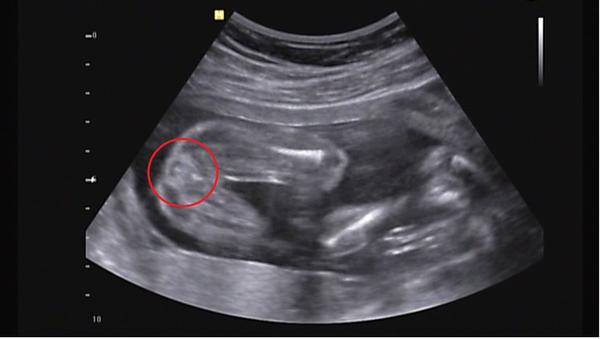

@gepe i podle té druhé fotky? mate mě to co je na fotce v kroužku...přijde mi to jako pytlík, ale to se mi zdá zas až moc dole, takže opravdu nevím :(

je to chlapeček nebo holčička ?

MUZETE PROSIM PORADIT I ME?? NA VIDEU JE POHLAVI SPISE AZ NA KONCI CCA 7MINUTA- tady je-